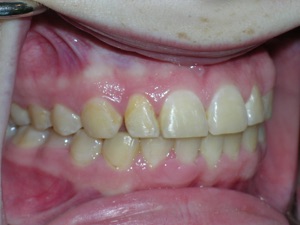

Here’s a fascinating case of a young lady who had a completely blocked out premolar.

With a combination of braces, expansion and trimming we were able to bring it in. Watch!

Here are the results.